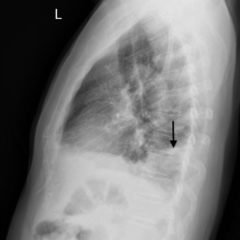

Hampton’s Hump in Pulmonary Embolism